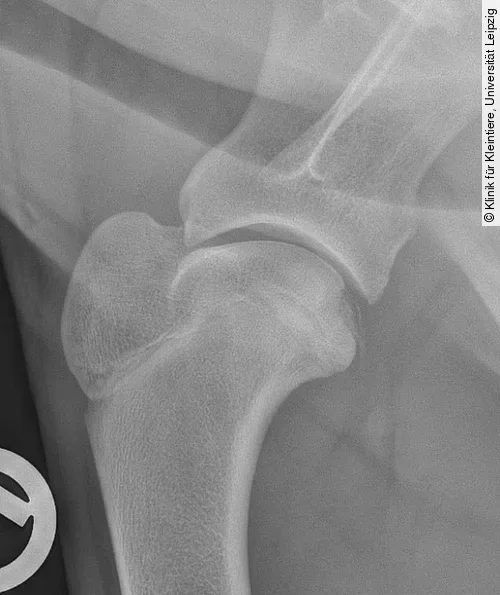

Projektionsradiografie Kniegelenk

Für die Darstellung der OCD am lateralen und medialen Condylus femoris wird eine mediolaterale und eine kraniokaudale oder kaudokraniale Röntgenaufnahme benötigt. Obwohl die mediolaterale Aufnahme häufig schon pathognomonische Anzeichen der OCD zeigt, ist eine kraniokaudale oder kaudokraniale Projektion erforderlich, um festzustellen, welcher Kondylus betroffen ist [4].

Die Röntgenbilder können Veränderungen wie eine Abflachung der Gelenkoberfläche an einem der beiden Femurkondylen (meist Medialfläche lateraler Kondylus), einen konkaven Defekt am subchondralen Knochen (mit oder ohne angrenzende Sklerose) oder selten mineralisierte Knorpelschuppen zeigen (Abb. [ 6 ], Abb. [ 7 ]).

Differenzialdiagnostisch kann es zu einer Verwechslung der normalen Fossa extensoria (Ursprung M. extensor digitorum longus) mit einer OCD-Läsion kommen. Die Fossa resultiert aber im Gegensatz zur OCD-Läsion nicht in einem Defekt der Gelenkfläche (kraniokaudale Projektion) und ist auf der mediolateralen Aufnahme deutlich weiter kranial und proximal lokalisiert (Abb. [ 6 ]) [4], [22].